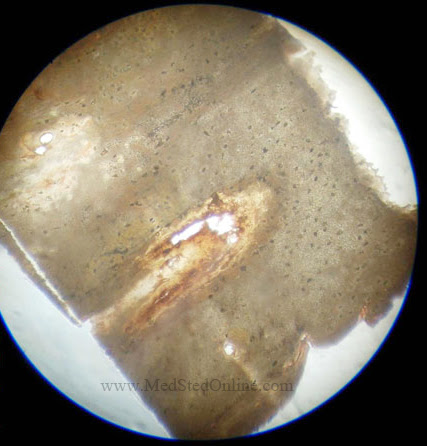

1styear MBBS histology

1styear MBBS Histology Diagrams (Printed)